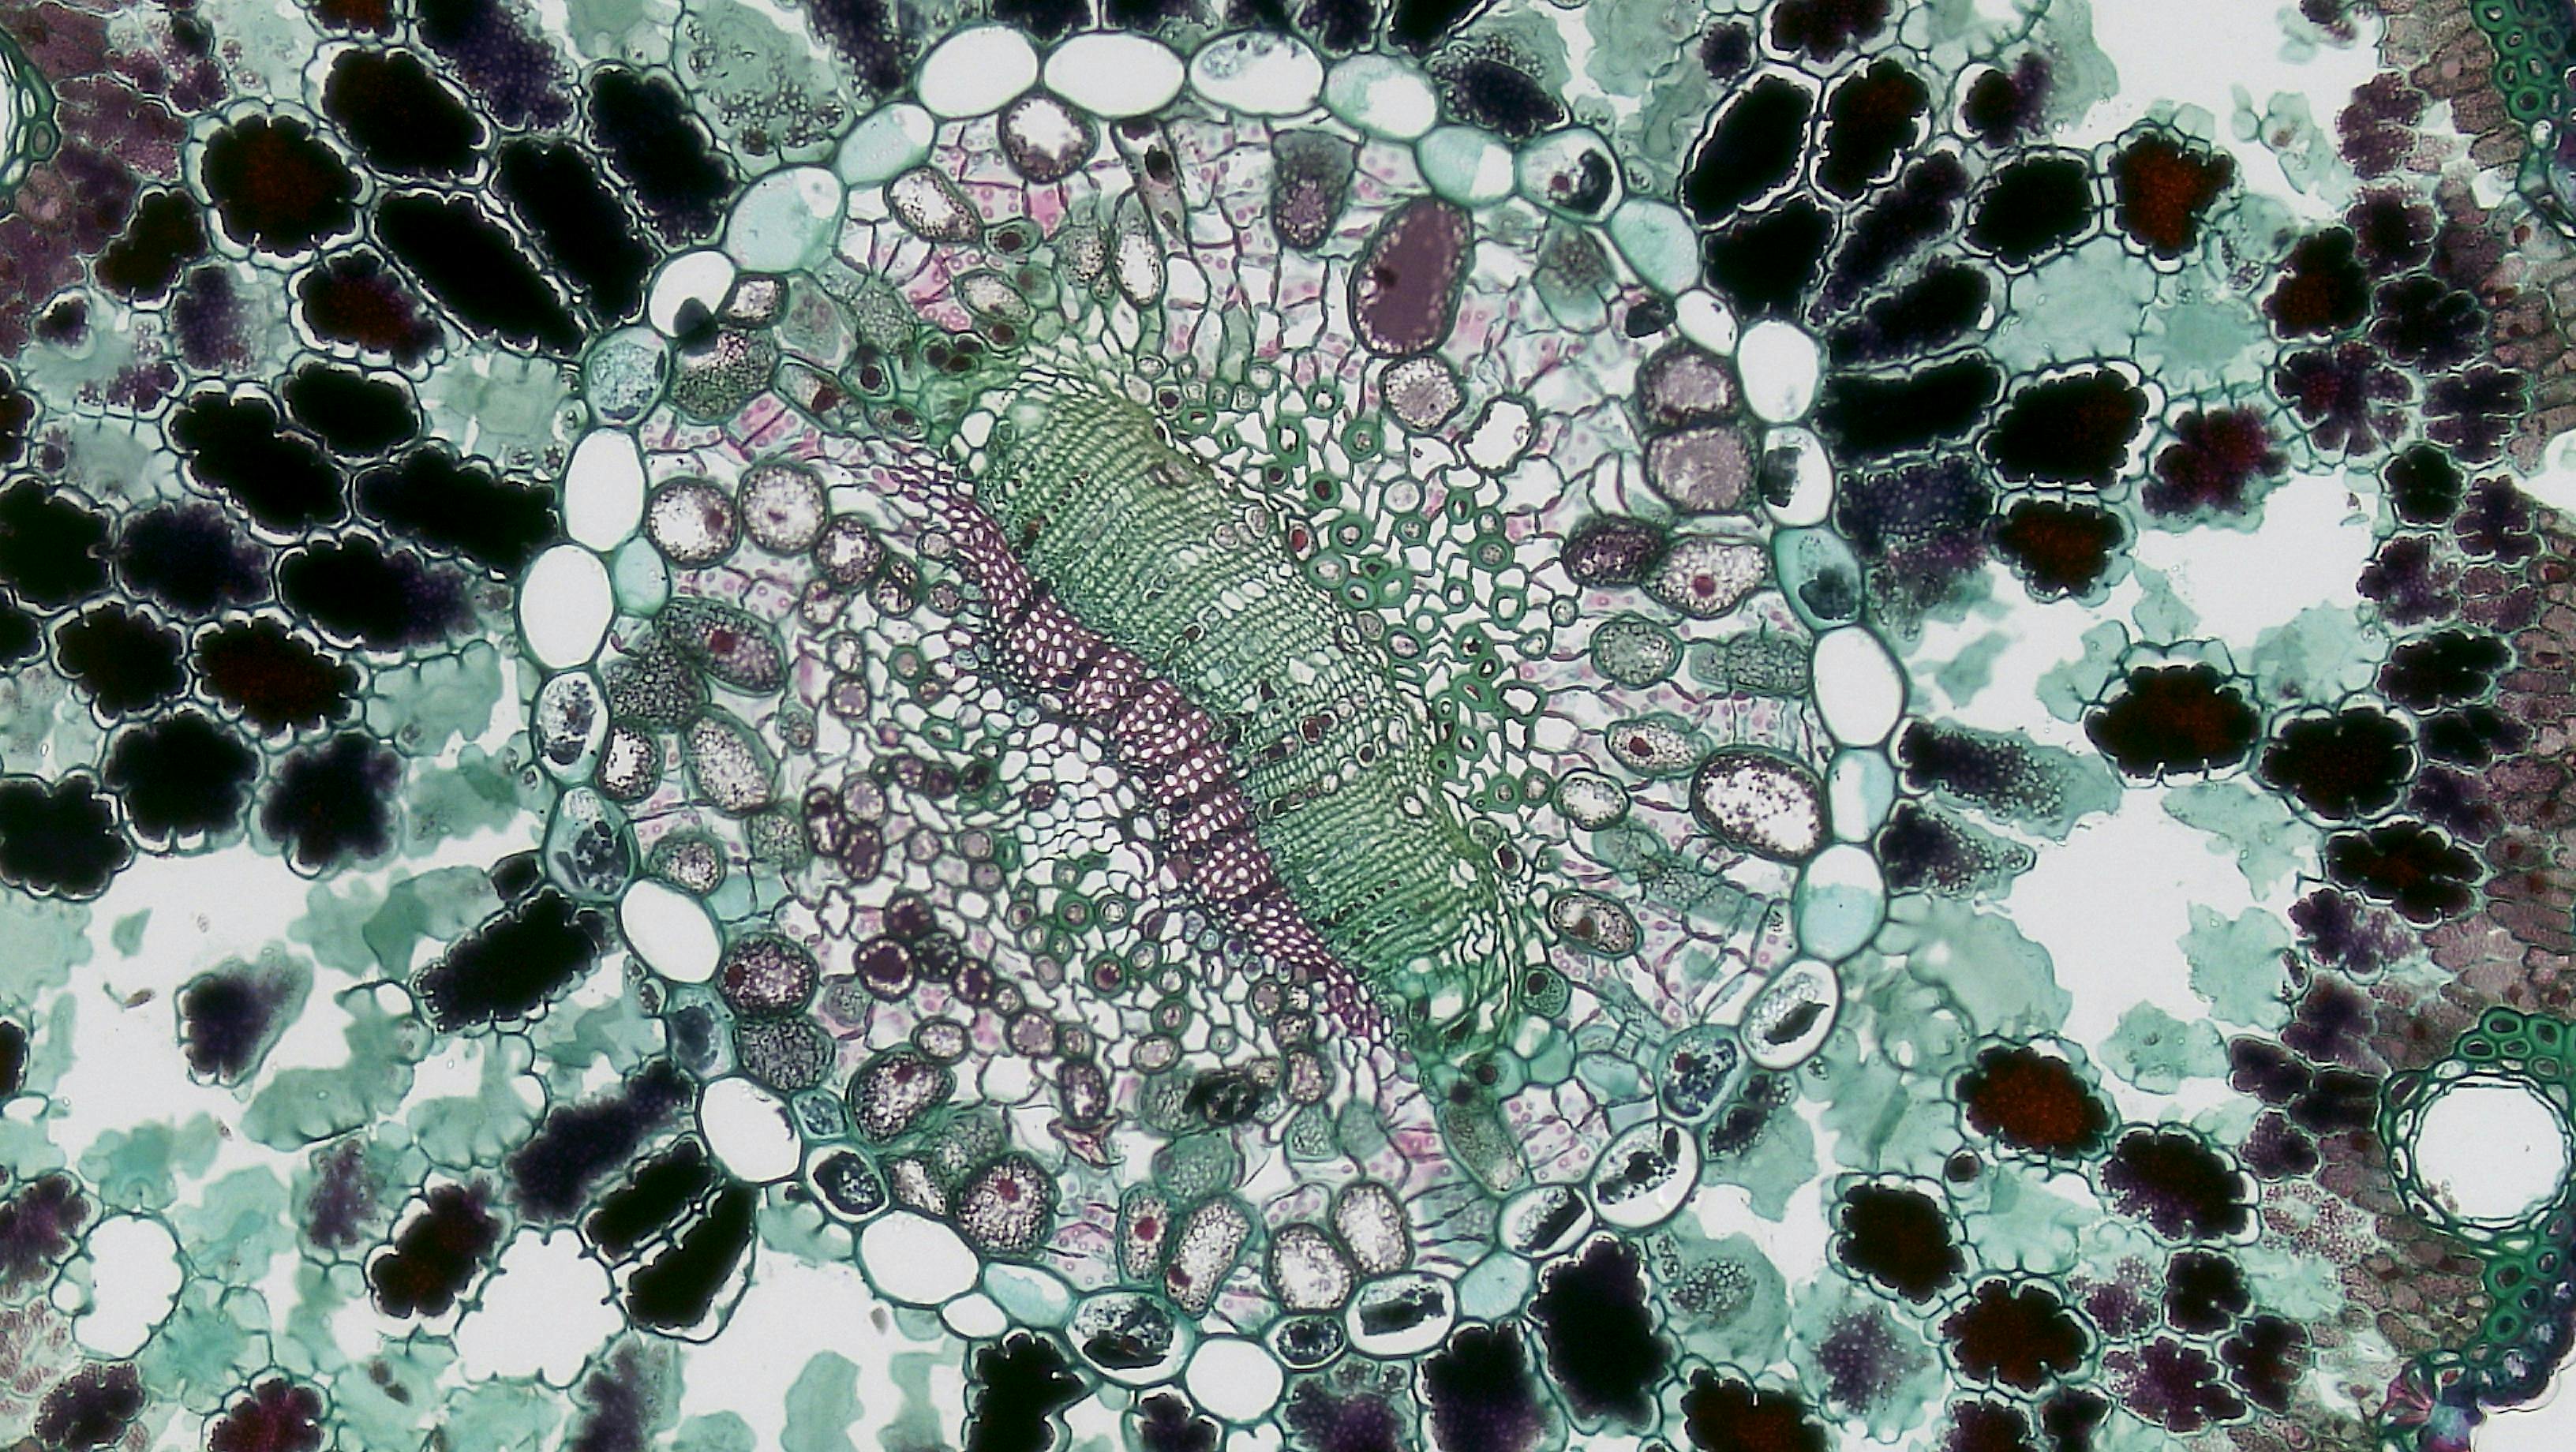

이 칩은 1,000개 이상의 암세포 덩어리를 혈관 세포와 함께 배양하며, 연구자가 원하는 시점에 특정 암세포를 선택적으로 회수할 수 있어 암세포가 치료제에 내성을 가지는 과정을 세밀하게 추적할 수 있습니다.

연구진은 오드세이 칩을 활용하여 유방암 치료제인 타목시펜에 대한 내성 형성 과정을 분석했습니다.

이를 통해 암세포가 어떻게 내성을 획득하는지, 그리고 이 과정에서 어떤 생물학적 원리가 작용하는지를 밝혀냈습니다.

특히, 암세포와 주변 혈관 세포 간의 복잡한 상호작용이 내성 획득에 중요한 역할을 한다는 사실이 드러났습니다.